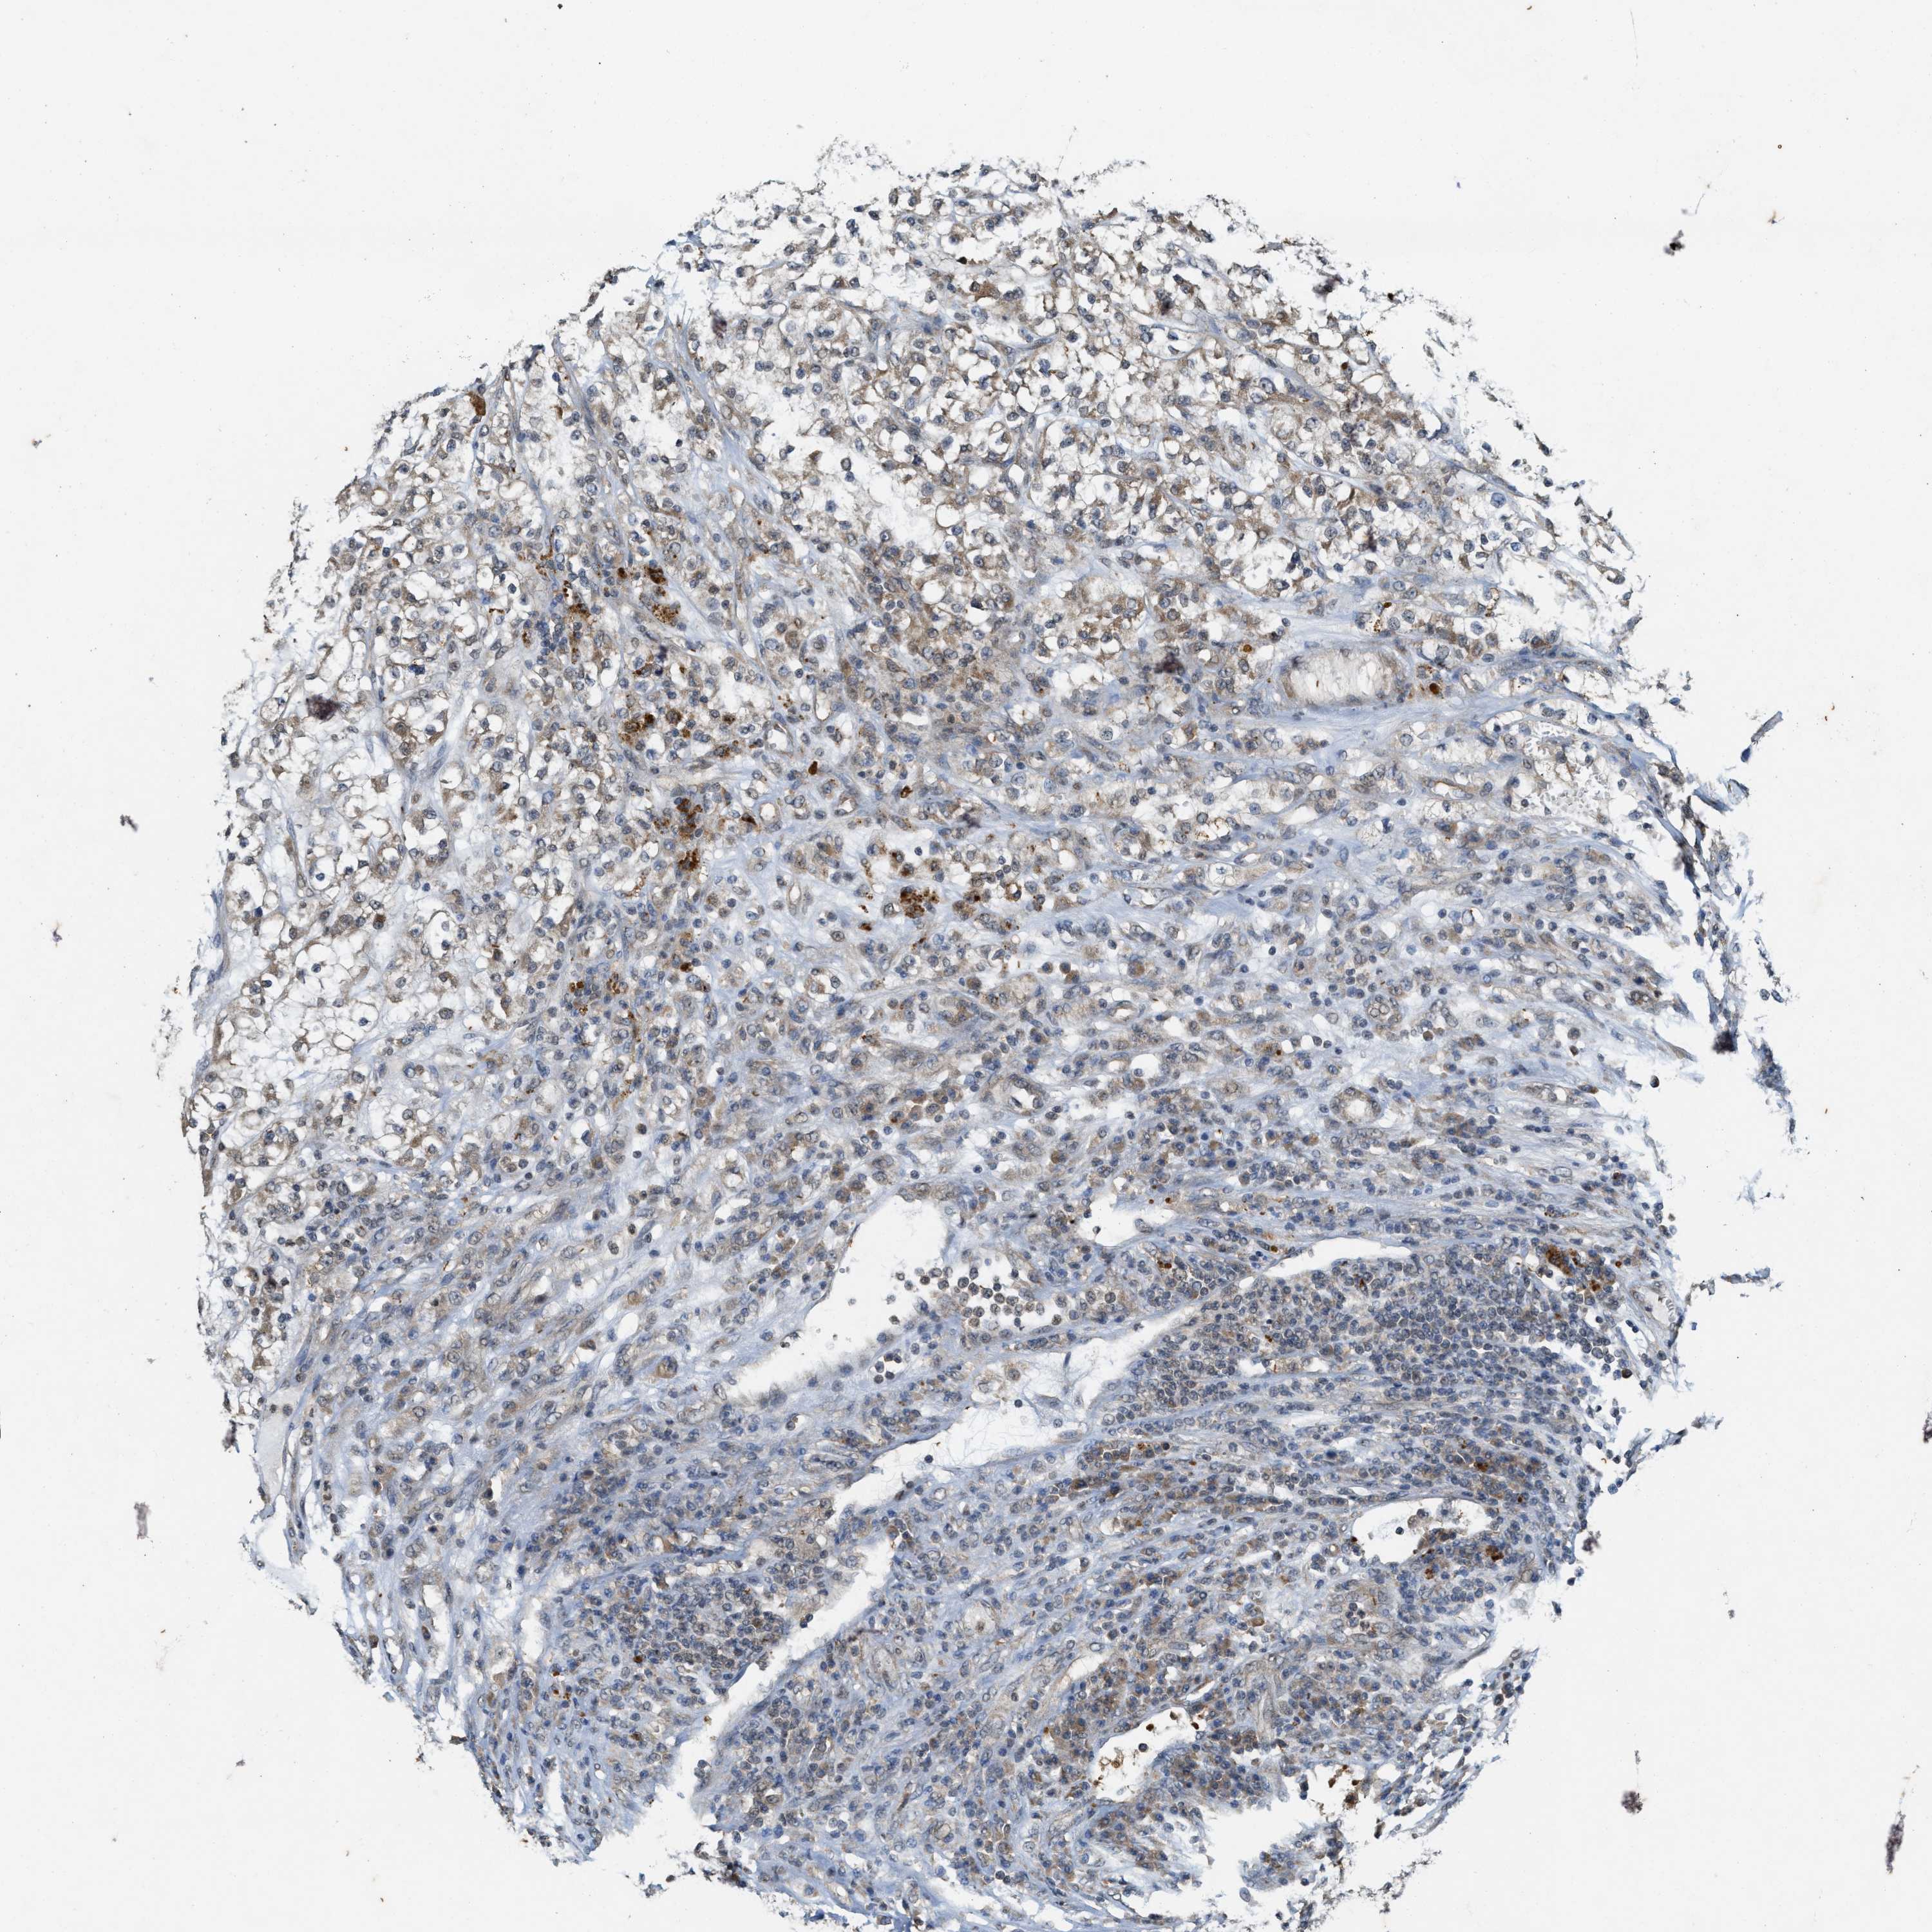

KIDNEY RENAL CLEAR CELL CARCINOMA (VALIDATION) - Interactive survival scatter ploti

The Survival Scatter plot shows the clinical status (i.e. dead or alive) for all individuals in the patient cohort, based on the same data that underlies the corresponding Kaplan-Meier plots. Patients that are alive at last time for follow-up are shown in blue and patients who have died during the study are shown in red.

The x-axis shows the expression levels (FPKM) of the investigated gene in the tumor tissue at the time of diagnosis. The y-axis shows the follow-up time after diagnosis (years). Both axes are complimented with kernel density curves demonstrating the data density over the axes. The top density plot shows the expression levels (FPKM) distribution among dead (red) and alive patients (blue). The right density plot shows the data density of the survived years of dead patients with high and low expression levels respectively, stratified using the cutoff indicated by the vertical dashed line through the Survival Scatter plot. This cutoff is automatically defined based on the FPKM cutoff that minimizes the p-score. The cutoff can be changed by dragging the vertical line or by entering a cutoff value in the square labeled "Current cut-off".

Under the Survival Scatter plot the p-score landscape (black curve; left axis) is shown together with dead median separation (red curve; right axis). Dead median separation is the difference in median mRNA expression between patients who have died with high and low expression, respectively. It is calculated as follows: median FPKM expression of dead patients with high expression - median FPKM expression of dead patients with low expression. This is intended to aid the user in visually exploring custom cutoffs and the associated p-scores and dead median separation.

Individual patient data is displayed and can be filtered by clicking on one or more of the category buttons on the top of the page. Categories describing expression level and patient information include: high, low, alive, dead, female, male and tumor stages. The scale of the x-axis can be toggled between linear and log-scale by clicking on the "x log" button. Mouse-over function shows TCGA ID, patient information and mRNA expression (FPKM) for each patient.

& Survival analysisi

Kaplan-Meier plots summarize results from analysis of correlation between mRNA expression level and patient survival. Patients were divided based on level of expression into one of the two groups "low" (under cut off) or "high" (over cut off). X-axis shows time for survival (years) and y-axis shows the probability of survival, where 1.0 corresponds to 100 percent.

KIF21A is not prognostic in Kidney Renal Clear Cell Carcinoma (validation)

Best expression cut offi

Based on the FPKM value of each gene, patients were classified into two groups and association between prognosis (survival) and gene expression (FPKM) was examined. The best expression cut-off refers the FPKM value that yields maximal difference with regard to survival between the two groups at the lowest log-rank P-value. Best expression cut-off was selected based on survival analysis .

When clicking on this number, the vertical dashed line indicating cut-off, the interactive survival plot, and the Kaplan-Meier curve will be adjusted to show results based on the best expression cut-off.

: 23.65

TCGA RNA samplesi

RNA-seq data is reported as average FPKM (number Fragments Per Kilobase of exon per Million reads), generated by the The Cancer Genome Atlas (TCGA) .

Normal distribution across the dataset is visualized with box plots, shown as median and 25th and 75th percentiles. Points are displayed as outliers if they are above or below 1.5 times the interquartile range. FPKM values of the individual samples are presented next to the box plot.

Average pTPM 27.2

Number of samples 100